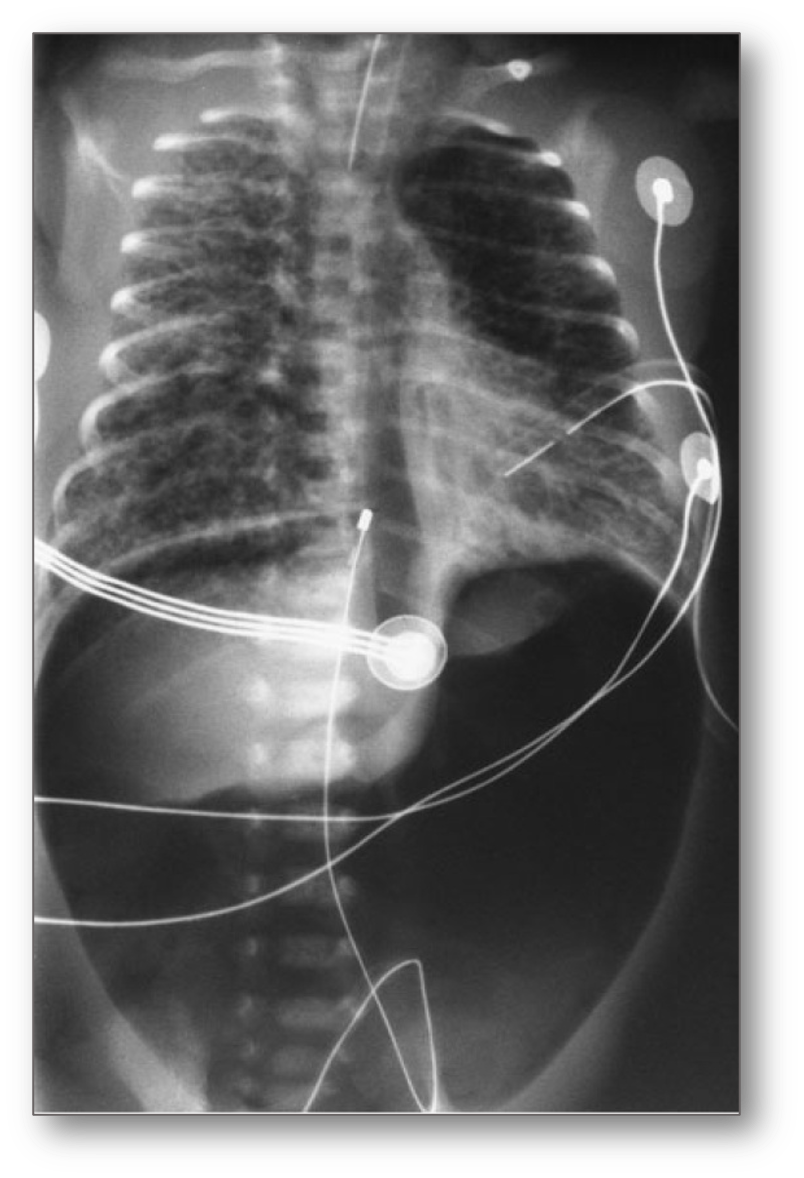

Pneumopericardium

With air completely surrounding the heart, demarcating the pericardial sac.